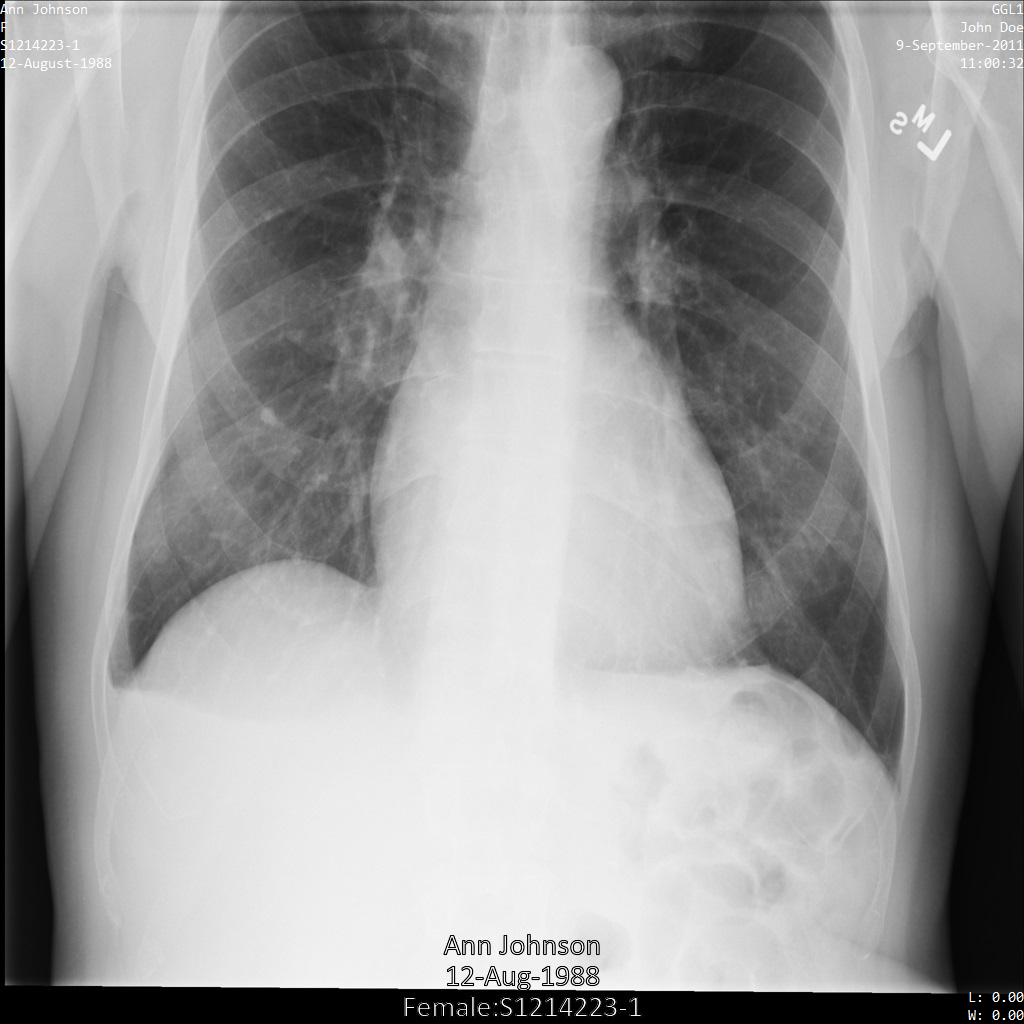

Beispielbild

Einige Beispiele auf dieser Seite enthalten eine Ausgabe des de-identifizierten Bildes. In jedem Beispiel wird das folgende Originalbild als Eingabe verwendet. Sie können das Ausgabebild jedes De-Identifizierungsvorgangs mit diesem Originalbild vergleichen, um die Auswirkungen des Vorgangs zu sehen:

Nach der De-Identifikation des Bildes mit REDACT_ALL_TEXT sieht es so aus. Beachten Sie, dass der gesamte eingebrannte Text am unteren Rand des Bildes entfernt wurde.